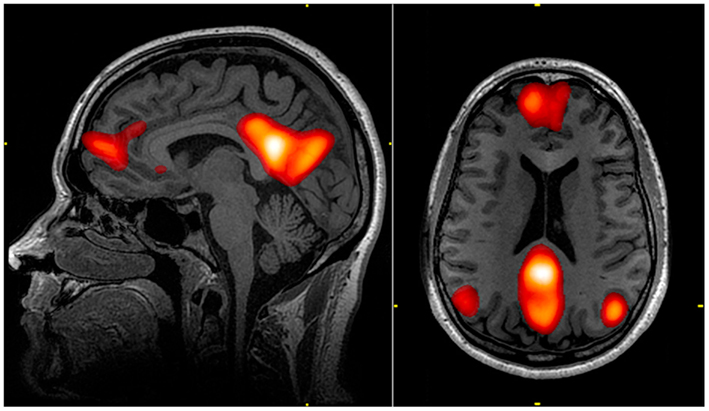

Cette pensée particulière stimule des zones denses en synapses dans le cerveau, au niveau du cortex pré-moteur. Toutes les actions, comme attraper la raquette, frapper la balle ou observer son mouvement sont imaginées. Ce pic d’activité est alors observé grâce à l’IRM fonctionnelle.

Le Dr Owen a par la suite commencé à utiliser l’IRM fonctionnelle qui, contrairement aux scanners ou IRM classiques qui rendent un cliché instantané, permet de suivre l’évolution de l’activité cérébrale, comme sur une vidéo, et en temps réel. Les zones actives sont repérées grâce à la quantité d’oxygène qu’elles utilisent.

Cliché d'IRM fonctionnelle du cerveau (Wikimedia Commons)

« J’ai encore la chair de poule quand je repense à ce qu’il s’est passé, confie le Dr Owen. Sur l’écran de contrôle, le cerveau de Scott s’est illuminé d’une myriade de couleurs. » Avec la permission de sa famille, il lui a immédiatement demandé s’il souffrait, après 12 ans d’état végétatif. Pour répondre « non », il lui a demandé d’imaginer un match de tennis. Le cerveau du patient s’est éclairé.